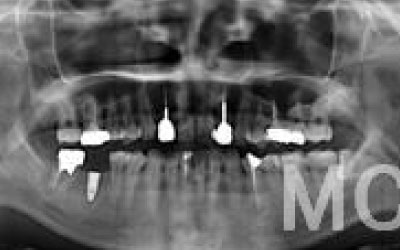

CTを使うことで、骨や歯の状態を3Dで確認でき、正確な距離測定も行えます。

骨の厚さや傾き、神経の位置などを事前にしっかりと計測することで、安全にインプラント治療を行うことができます。